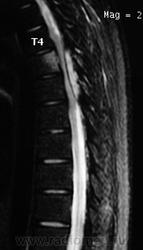

ГМ. СМ. Ганглионейробластома. +

Ганглионейробластома